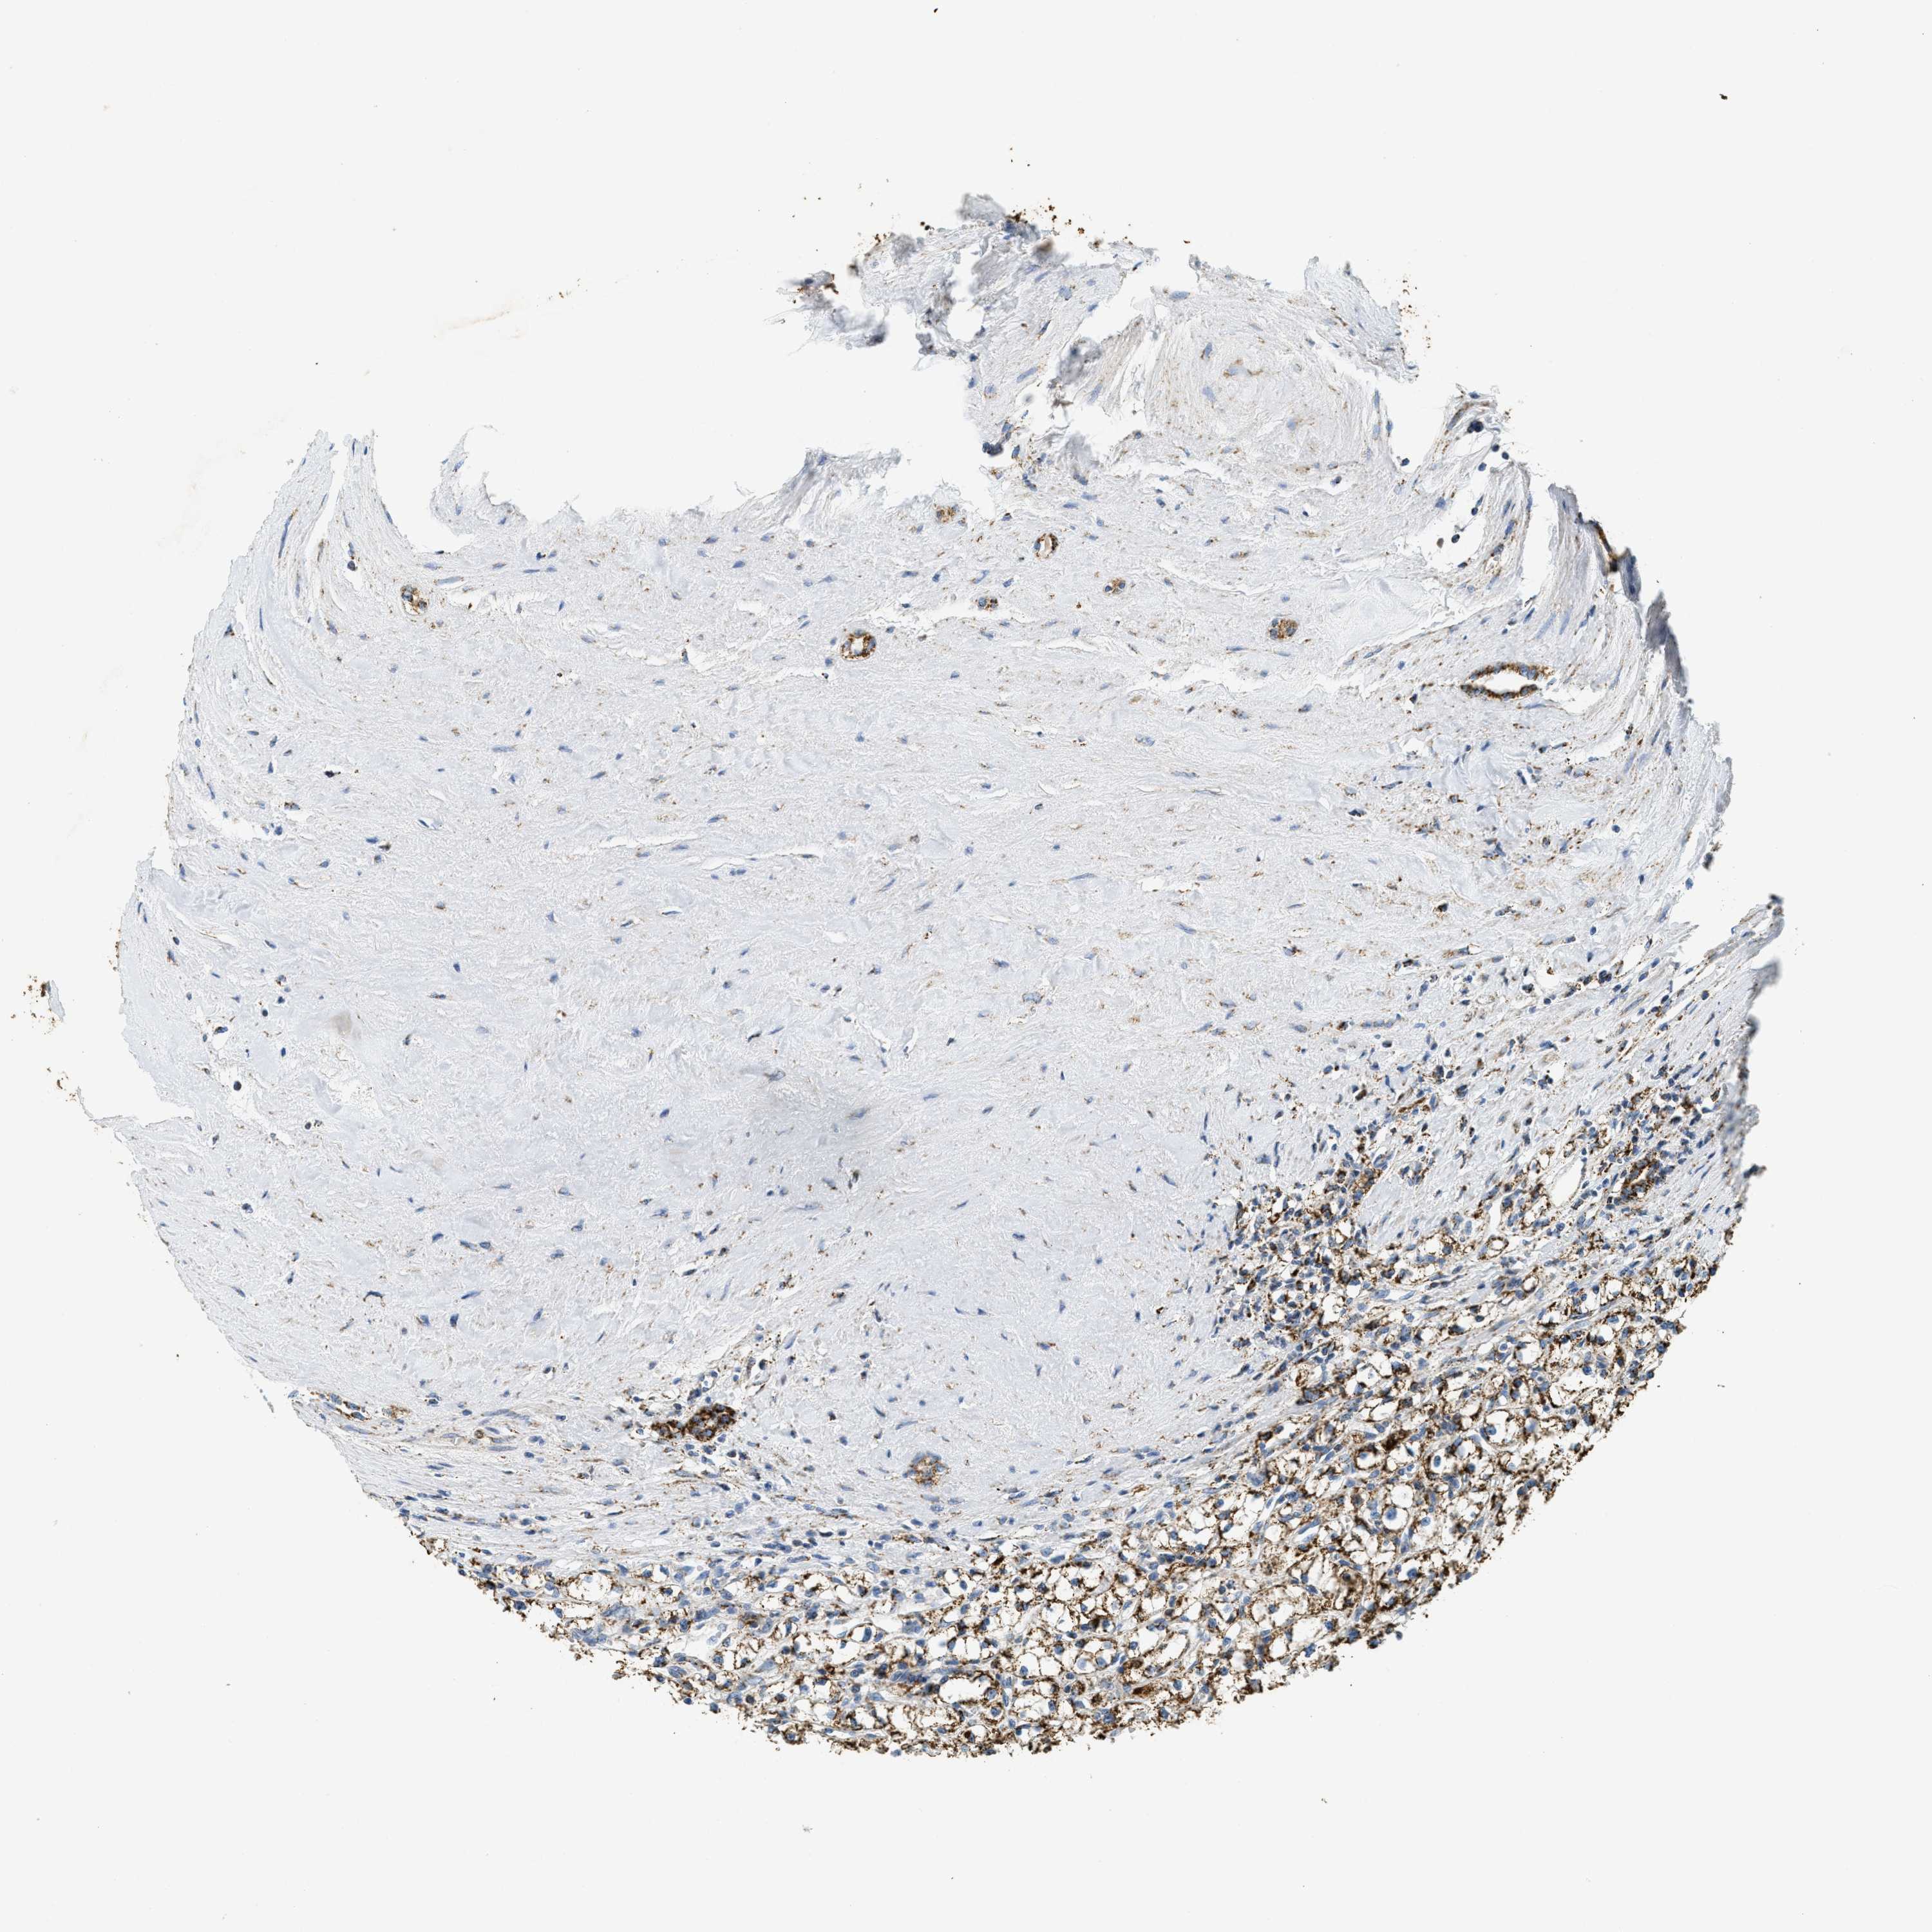

KIDNEY RENAL CLEAR CELL CARCINOMA (VALIDATION) - Interactive survival scatter ploti

The Survival Scatter plot shows the clinical status (i.e. dead or alive) for all individuals in the patient cohort, based on the same data that underlies the corresponding Kaplan-Meier plots. Patients that are alive at last time for follow-up are shown in blue and patients who have died during the study are shown in red.

The x-axis shows the expression levels (FPKM) of the investigated gene in the tumor tissue at the time of diagnosis. The y-axis shows the follow-up time after diagnosis (years). Both axes are complimented with kernel density curves demonstrating the data density over the axes. The top density plot shows the expression levels (FPKM) distribution among dead (red) and alive patients (blue). The right density plot shows the data density of the survived years of dead patients with high and low expression levels respectively, stratified using the cutoff indicated by the vertical dashed line through the Survival Scatter plot. This cutoff is automatically defined based on the FPKM cutoff that minimizes the p-score. The cutoff can be changed by dragging the vertical line or by entering a cutoff value in the square labeled "Current cut-off".

Under the Survival Scatter plot the p-score landscape (black curve; left axis) is shown together with dead median separation (red curve; right axis). Dead median separation is the difference in median mRNA expression between patients who have died with high and low expression, respectively. It is calculated as follows: median FPKM expression of dead patients with high expression - median FPKM expression of dead patients with low expression. This is intended to aid the user in visually exploring custom cutoffs and the associated p-scores and dead median separation.

Individual patient data is displayed and can be filtered by clicking on one or more of the category buttons on the top of the page. Categories describing expression level and patient information include: high, low, alive, dead, female, male and tumor stages. The scale of the x-axis can be toggled between linear and log-scale by clicking on the "x log" button. Mouse-over function shows TCGA ID, patient information and mRNA expression (FPKM) for each patient.

& Survival analysisi

Kaplan-Meier plots summarize results from analysis of correlation between mRNA expression level and patient survival. Patients were divided based on level of expression into one of the two groups "low" (under cut off) or "high" (over cut off). X-axis shows time for survival (years) and y-axis shows the probability of survival, where 1.0 corresponds to 100 percent.

HLCS is not prognostic in Kidney Renal Clear Cell Carcinoma (validation)

Best expression cut offi

Based on the FPKM value of each gene, patients were classified into two groups and association between prognosis (survival) and gene expression (FPKM) was examined. The best expression cut-off refers the FPKM value that yields maximal difference with regard to survival between the two groups at the lowest log-rank P-value. Best expression cut-off was selected based on survival analysis .

When clicking on this number, the vertical dashed line indicating cut-off, the interactive survival plot, and the Kaplan-Meier curve will be adjusted to show results based on the best expression cut-off.

: 7.7

Median expressioni

Median expression refers to the median FPKM value calculated based on the gene expression (FPKM) data from all patients in this dataset. When clicking on this number, the vertical dashed line indicating cut-off, the interactive survival plot, and the Kaplan-Meier curve will be adjusted to show results based on the median expression.

: N/A

Median follow up timei

Median follow up time refers to the median time (years) after diagnosis with this type of cancer, based on clinical data from all patients in this dataset.

P scorei

Log-rank P value for Kaplan-Meier plot showing results from analysis of correlation between mRNA expression level and patient survival.

N/A

5-year survival highi

5-year survival for patients with higher expression than the expression cutoff.

For melanoma and glioma, 3-year survival is shown.

5-year survival lowi

5-year survival for patients with lower expression than the expression cutoff.

TCGA RNA samplesi

RNA-seq data is reported as average FPKM (number Fragments Per Kilobase of exon per Million reads), generated by the The Cancer Genome Atlas (TCGA) .

Normal distribution across the dataset is visualized with box plots, shown as median and 25th and 75th percentiles. Points are displayed as outliers if they are above or below 1.5 times the interquartile range. FPKM values of the individual samples are presented next to the box plot.

Average pTPM 8.3

Number of samples 100